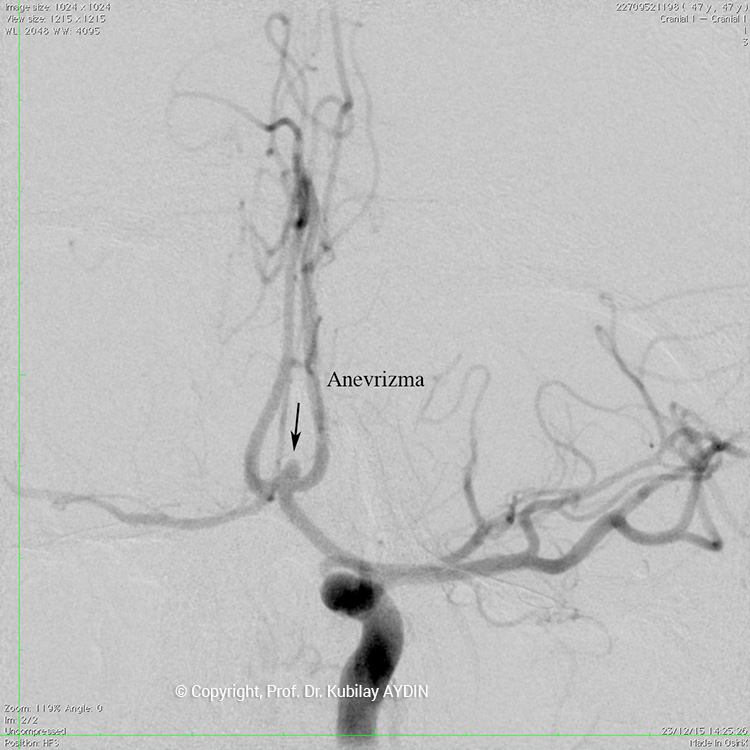

Geniş boyunlu anevrizmaların stent kullanılarak koillerle kapatılması işlemine “stent-yardımlı koilleme” adını veriyoruz. Bu işlemin ilk aşamasında anevrizmanın boynunu örtecek şekilde damar içine bir metal kafes (stent) yerleştirilerek, bir sonraki aşamada anevrizma kesesi içine konulan koillerin damar içine sarkması önlenir. Yani, burada stentin görevi, anevrizma içine doldurduğumuz koil adı verilen tellerin, damar içine sarkmasını önlemektir. Stent-yardımlı koilleme, geniş boyunlu anevrizmaların kapalı yöntemle tedavisinde tercih edilen bir yöntemdir.

Stent yardımlı koilleme tekniği ile anevrizma tedavisinde, anevrizmanın yerleştiği atardamar içerisine stent açılması için bir kateter yerleştirilir. Eş zamanlı olarak, anevrizma kesesi içerisine koilleme amaçlı farklı bir kateter yerleştilir. Damar içerisine bir stent açıldıktan sonra, anevrizma içerisideki kateterden gönderilen platinden yapılmış çok yumuşak yapıda koillerle anevrizma kesesi doldurulur. Stent, anevrizma içeriside bırakılan koillerin damar içine sarkmasına engel olur. Koilleme işlemine, anevrizma koillerle tamamen doldurulana ve anevrizma içine kan girmeyene kadar devam edilir.